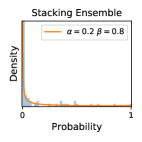

5.1 Distribution of Uncertainty Scores

Distribution of Uncertainty Scores Across Different Severity Levels As explained in Section 3, each uncertainty metric essentially defines an order/ranking among the data points. We conducted an analysis to better understand what data will be assigned high uncertainty under a particular uncertainty metric . Picking out the highest ranked data points (), we calculated the ratio of data points from each SL. Figure 4 summarizes the results as box plots for the Kaggle-DR and the Messidor-2 datasets; additional detailed statistics can be found in Table S.1 in the supplementary materials. From the plot and table, SL1 & SL2 examples account for a higher proportion among the top-ranked uncertain examples across the three ensemble methods. This finding matches our intuition that incipient disease examples (SL1 & SL2) are more likely to be considered uncertain by ensemble methods due to their ambiguity.

False Negatives vs. Uncertain Negatives As discussed in Section 2, the FNP measures the probability of the identified uncertain negatives being actual false negatives. The higher the FNP, the more wrong predictions an uncertainty-informed scheme can potentially correct. In Figures 3b, we report the FNP values under different settings from different combinations of ensemble methods and uncertainty metrics. The results in uncertain false negatives and their ratios to the number of uncertain negatives are illustrated in Figures 3a & 3b, respectively. mean gives higher false negative precision values than var, which validates Theorem 1.

Comparing the three ensemble methods in Figure 4, the stacking ensemble method has the highest ratios of SL1 & SL2 data among the high-uncertainty examples it identified under both mean and var. TTA showed slightly better performance than MC-dropout but still falls behind the stacking ensemble method. Considering the fact that SL0 examples accounted for the majority of the dataset, the stacking ensemble method was much more precise (specific) in selecting truly ambiguous data points that were difficult to classify. From Figure 3, we can also see that the stacking ensemble method greatly outperformed the other two methods in finding false negatives under both mean and var uncertainty metrics.

In contrast, the MC-dropout method showed the worst overall performance among the three, as it can be seen from the high ratios of SL0 examples among the uncertain negatives in Figure 4. The histograms in Figure 2 provides another perspective to look into the phenomenon, where a decent proportion of MC-dropout model’s predictions on SL0 inputs entailed low confidence (far from 0 or 1), which from another angle explained why MC-dropout was less specific in terms of lower FNP; many no-DR inputs (i.e. SL0) were erroneously assigned high uncertainty by MC-dropout models.

As discussed in Section 5.1 and Section 5.3 in the main paper, the mean metric and the stacking ensemble will have better performance in the precision (specificity) on the ambiguous data. Here, more detailed results are shown in Figures S.3 & S.6 and Table S.1. Figures S.3 & S.4 show the histograms of the uncertainty score for Kaggle-DR and Messidor-2 datasets that are the in-distribution (i.d.) dataset in our experiment and FigureS.5 & S.6 show the histograms for ImageNet and CIFAR-10 datasets, which is the o.o.d. datasets in our experiment. Each group of histograms contains results from the three evaluated ensemble methods (stacking ensemble, MC-dropout and TTA) and the three uncertainty metrics (mean, var and kl). Additional detailed results not displayed in Figure 4 can be found in Table S.1, which shows the proportion of the data of different SLs varies across different . For comparison, we also included in Table S.1 the results from single learners, and the proportions of data of different SLs (before any selection was made).